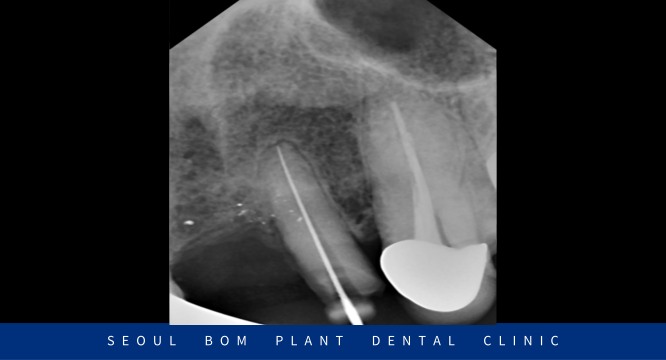

앞니 보철물 수복이 마무리된 구강 내 사진인데요.

환자분께서는 색상, 모양 모두 마음에 드신다며

바로 붙여달라고 하셨지만

자연광이나 밝고 어두운 곳에서의 색상도 확인해 보는 것이 좋다고 판단되어

임시로 접착하여 일생 생활에서 사용해 보시면서

거슬리거나 불편한 부분이 없는지 체크해 본 다음에

완전히 붙여드리기로 하였습니다.

며칠 사용해 보시더니 불편한 거 없으셨고

치료 전보다 훨씬 더 심미적으로 변해서

오히려 마음에 든다며 말씀해 주셔서

보철물을 완전히 붙여드리면서 치료를 마무리해 드렸습니다.